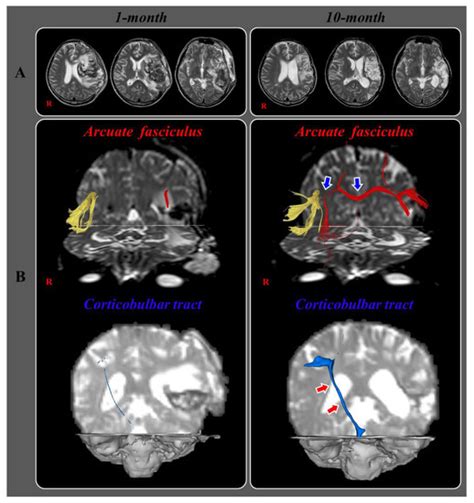

Diffusion Tensor Tractography Studies on Recovery Mechanisms of Aphasia ...